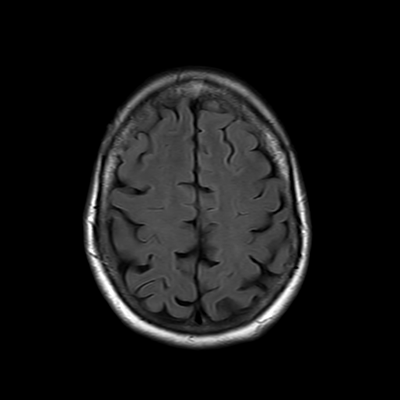

You also obtain an MRI of his brain once it's clinically safe to do so.

MRI brain (FLAIR)